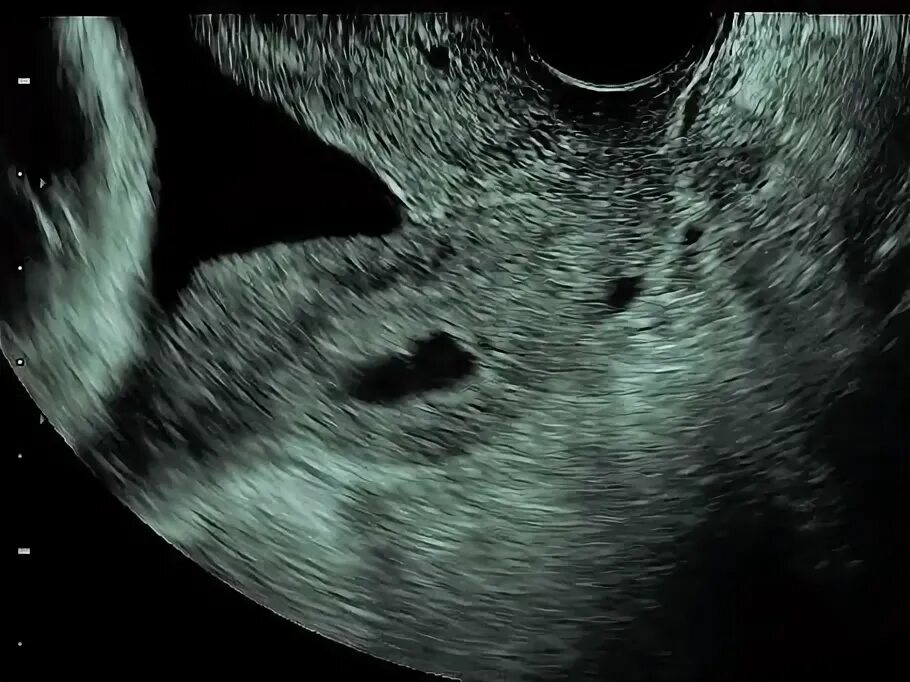

Внутренний зев воронкообразно